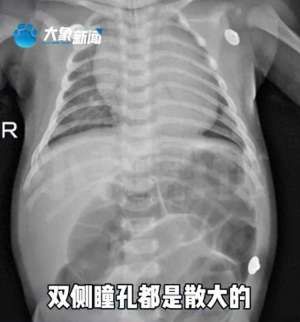

• 哄逗(52天宝宝中毒进ICU因奶奶喂水加了这种极常见食品其中风险必须了解→)

哄逗(52天宝宝中毒进ICU因奶奶喂水加了这种极常见食品其中风险必须了解→)

近日,河南省儿童医院接诊了一名仅52天的宝宝小林林(化名)小林林出现严重腹胀还出现了出现呼吸困难,情况十分危急!医生迅速为小林林进行气管插管和机械通气,解决了呼吸问题。然而,孩子的腹胀症状仍未缓解,且瞳孔...